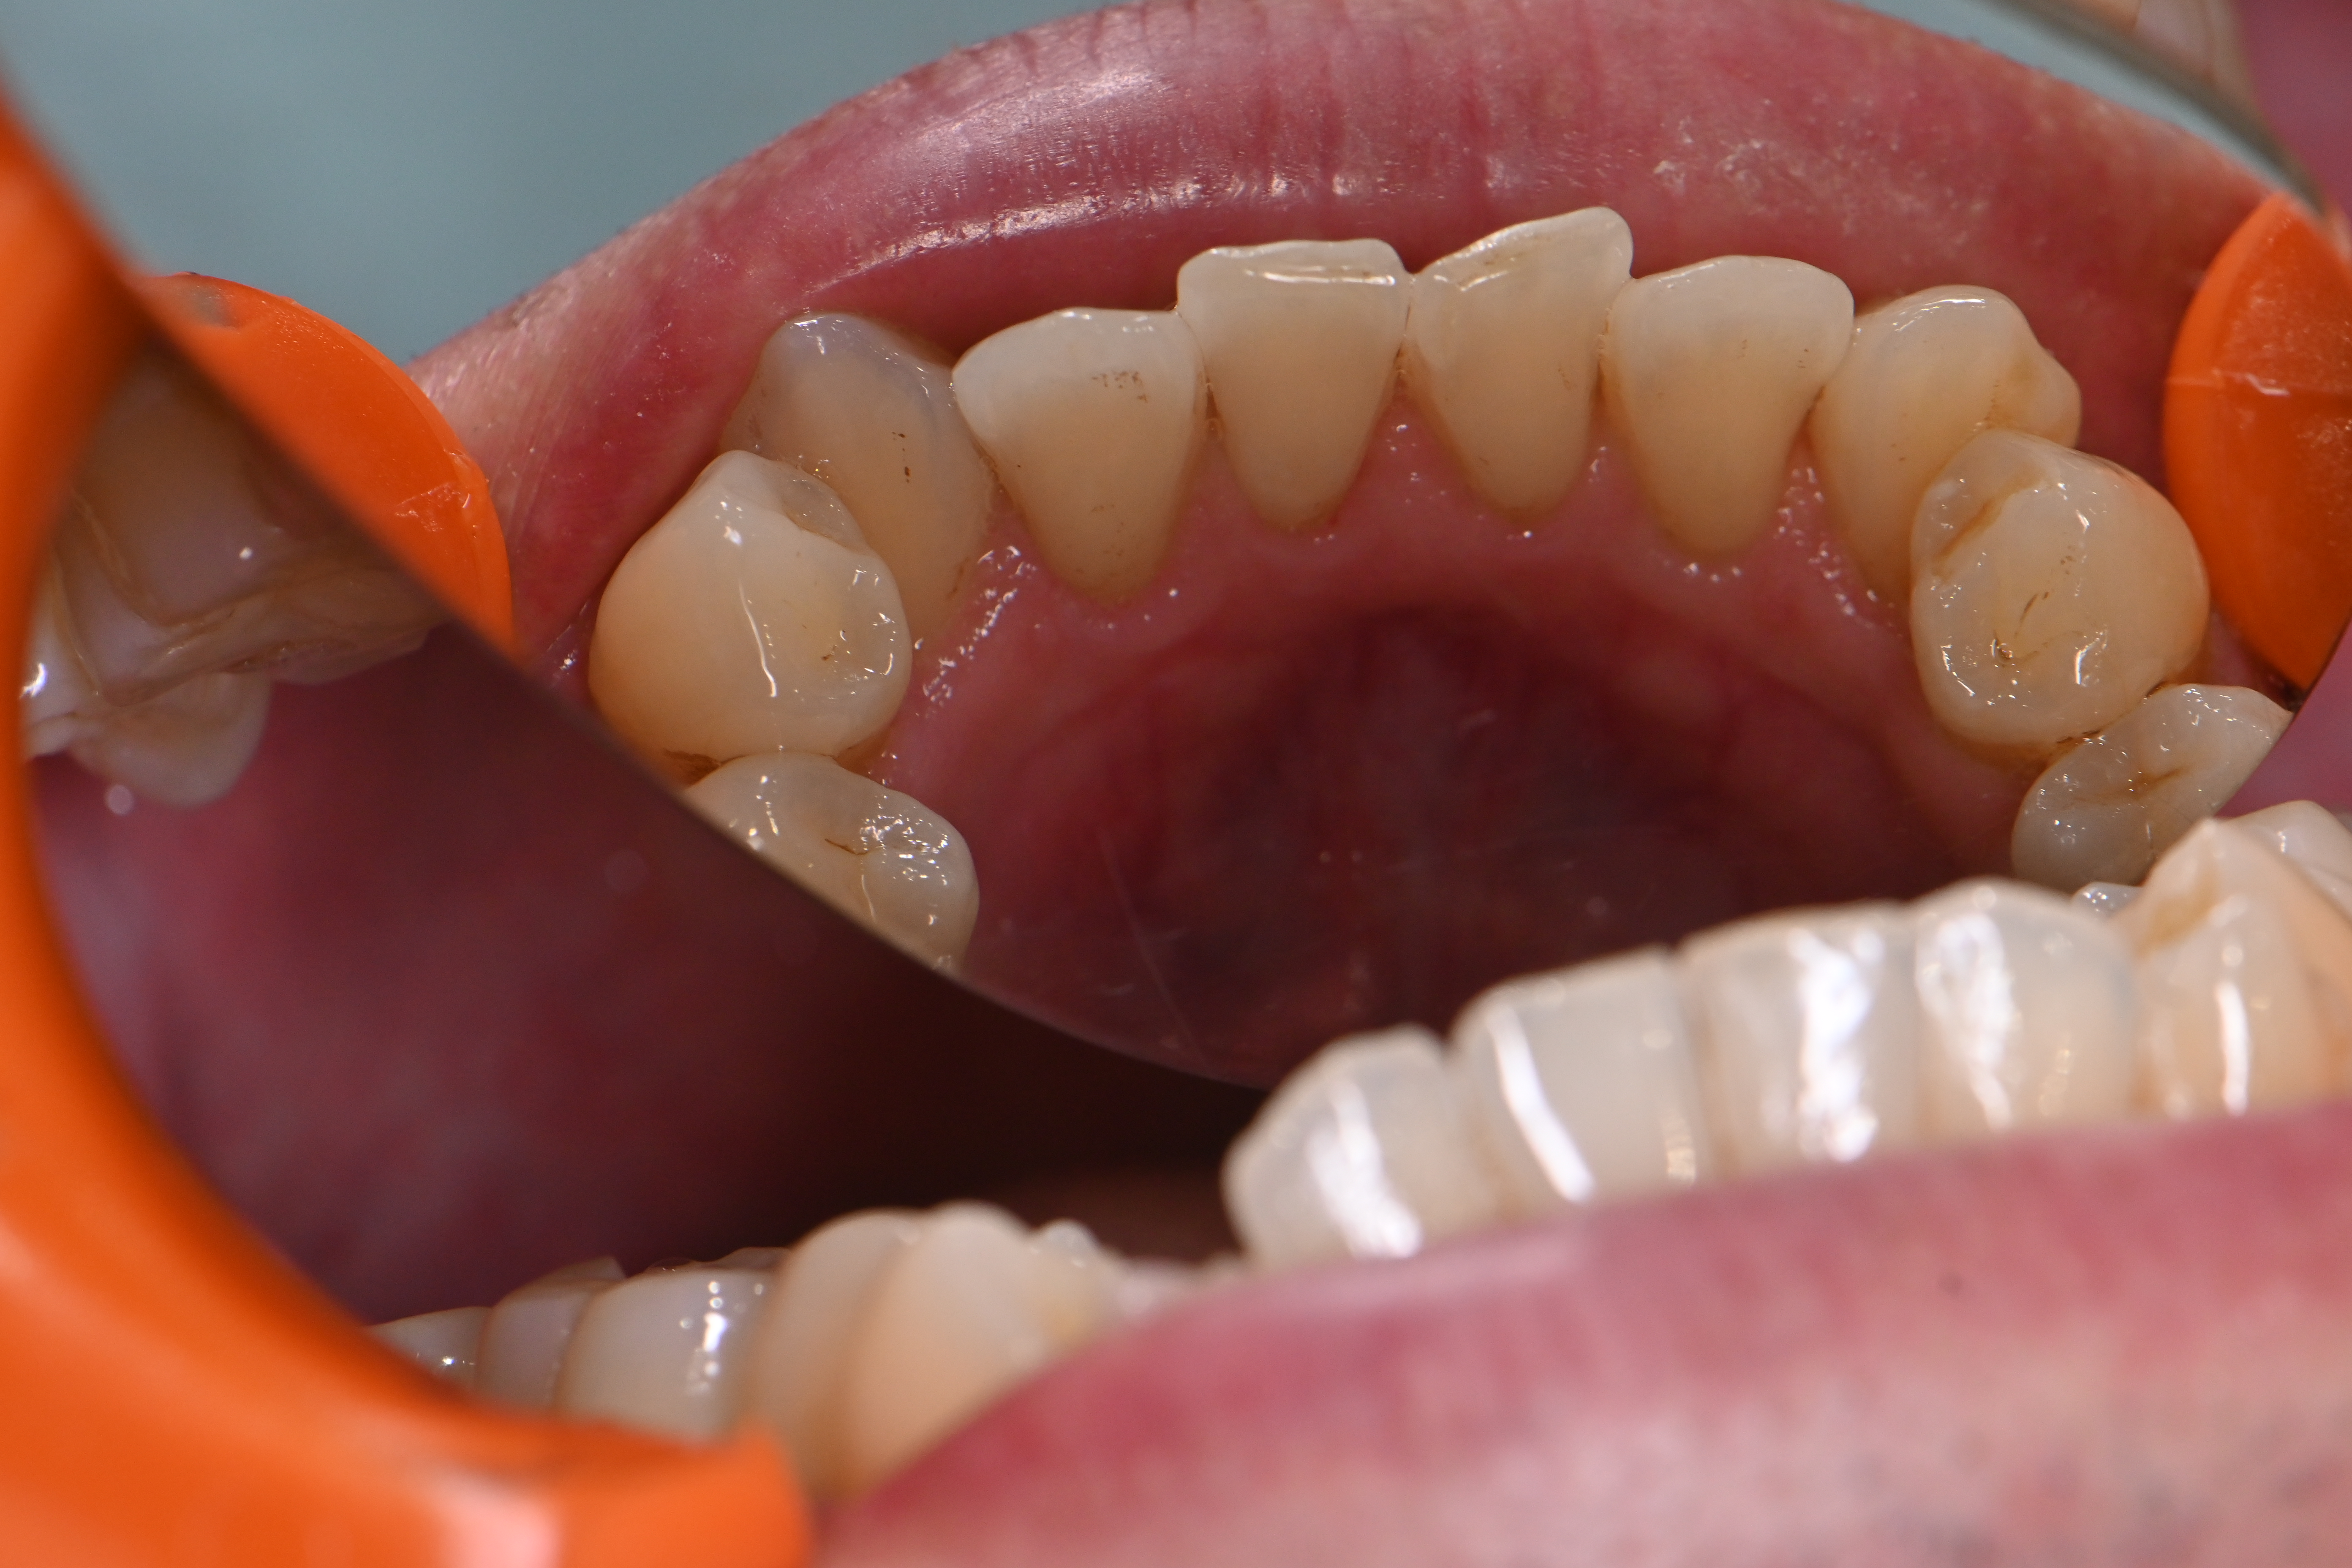

今回は全体的に着色が気になる方の症例です。

他の歯医者さんで以前からエアフローで着色を除去されてきた患者様ですが、前回してから半年期間が空いてしまったら再度着色が目立つようになったのこと💦

細かい着色をエアフローでしっかり除去して、仕上げにリナメル(歯の細かい傷を埋めてくれる)を塗布しました✨

場所によっては分厚い磨き残しがあり、そこに着色していた箇所もあったため歯磨き指導も一緒にさせていただきました。